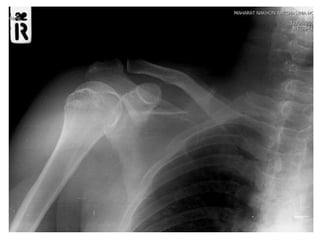

 Film right shoulder AP , transcapular

 Film right humerous AP , lateral

Right anterior shoulder dislocation

with avulsion fracture right greater

tuberosity

investigation  Film rightshoulder AP , transcapular  Film right humerous AP , lateral

Imp : Right anteriorshoulder dislocation with avulsion fracture right greater tuberosity